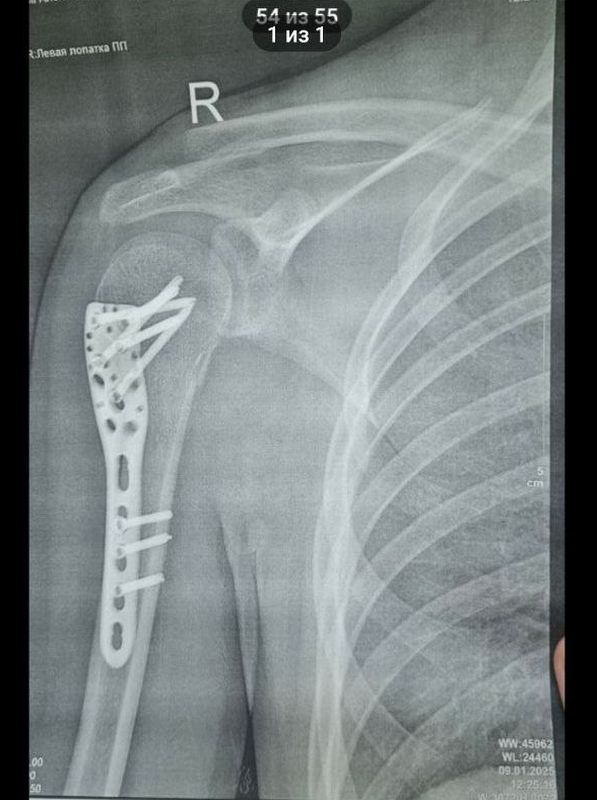

Парень получил перелом трубчатой кости плеча (хирургической шейки плеча), перелом отростка позвоночника: кроме того, пока точно не установлен диагноз после травмы ноги - или разрыв мениска, или хрящевой перелом левого коленного сустава. Парень пережил две операции. Одна, как рассказала корреспонденту портала «маленькая Сызрань» бабушка студента, прошла неудачно; при второй пареньку поставили в плечо пластину, к которой закрепили раздробленную мышцу и то, что осталось от сухожилий (на фото внизу)